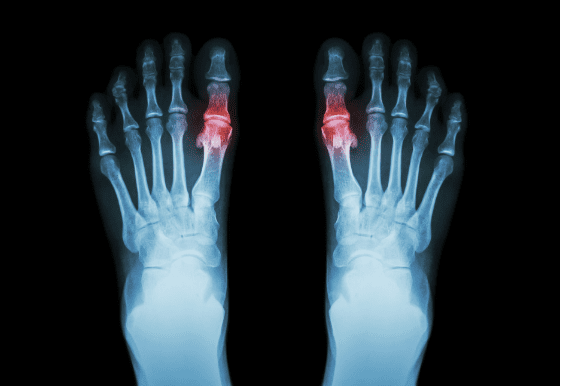

Arthritis

Arthritis can have a significant impact on your ability to stay comfortable and pain-free on your feet, and to move with confidence. It affects your joints, and does so in a range of ways depending on the type of arthritis you have. While there are over 140 different types of arthritis, the most common types seen by our podiatrists across our Brisbane City and Newmarket clinics include osteoarthritis, rheumatoid arthritis, gout, and juvenile idiopathic arthritis in children.

One of the distinguishing factors of the disease is that it typically affects the joints symmetrically, across multiple joints. The joints commonly involved include: the small joints of your hands and feet, knees, hips, ankles, elbows and shoulders. In some people, the disease will affect more than just your joints, and may cause damage to your skin, eyes, lungs, heart and blood vessels.

Rheumatoid arthritis tends to present in symptomatic ‘flares’, as opposed to the symptoms being constant over months or years. The most common symptoms of rheumatoid arthritis that we see during a flare include having painful and inflamed joints, stiffness or restricted movement at the joints, rheumatoid ‘nodules’, and changes to the shape of the joints over time. Joint inflammation is typically symmetrical, with multiple joints affected at the same time. Muscle and joint pain can also present with fatigue, fever and a loss of appetite.